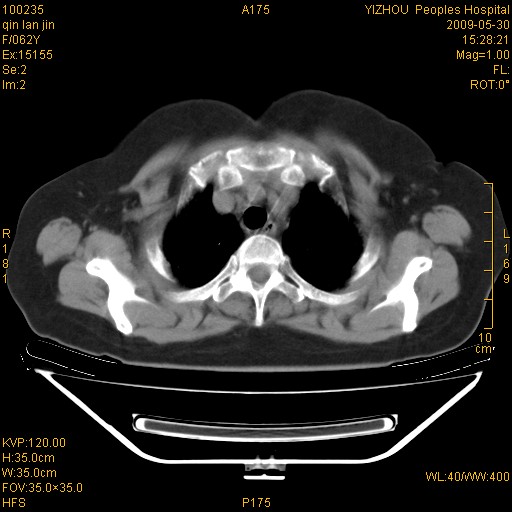

标题: CT20268:肺泡癌?间质性肺炎? [打印本页]

标题: CT20268:肺泡癌?间质性肺炎?

女,62岁,近二年经常咳嗽,近二个月,消瘦、乏力。

两肺弥漫性间质性病变(间质性肺炎伴肺间质纤维化?)。

支持弥漫性肺间质纤维化。

支持 特发性间质性肺炎【iip 】